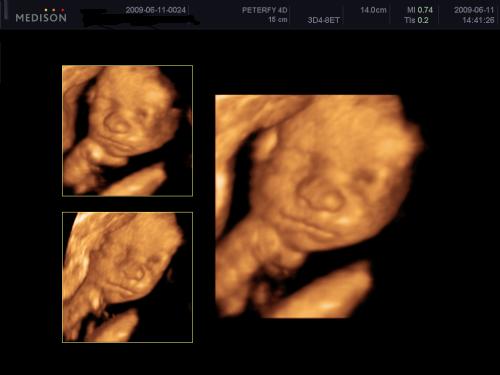

Kb. 3,5 hete én is voltam 4D-n és egy egész jó kis kép kerekedett belőle, majd felteszem.